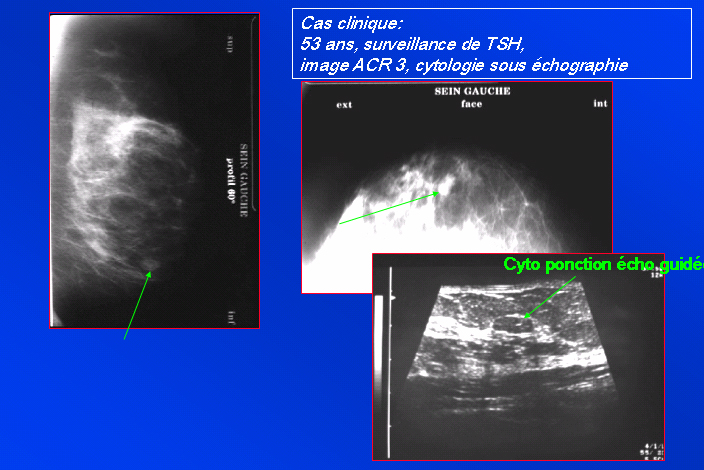

Vérifier la concordance mammographie-échographie | Iconographie précédente | Retour cours | Index iconographique | Iconographie suivante |